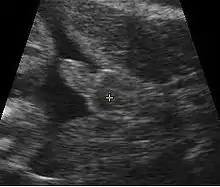

Fetus at 14 weeks (profile)

Obstetric sonography is useful in the assessment of the cervix in women at risk for premature birth. A short cervix preterm is associated with a higher risk for premature delivery: At 24 weeks' gestation, a cervix length of less than 25 mm defines a risk group for spontaneous preterm birth. Further, the shorter the cervix, the greater the risk.[19] Cervical measurement on ultrasound also has been helpful to use ultrasonography in patients with preterm contractions, as those whose cervical length exceeds 30 mm are unlikely to deliver within the next week.[20]